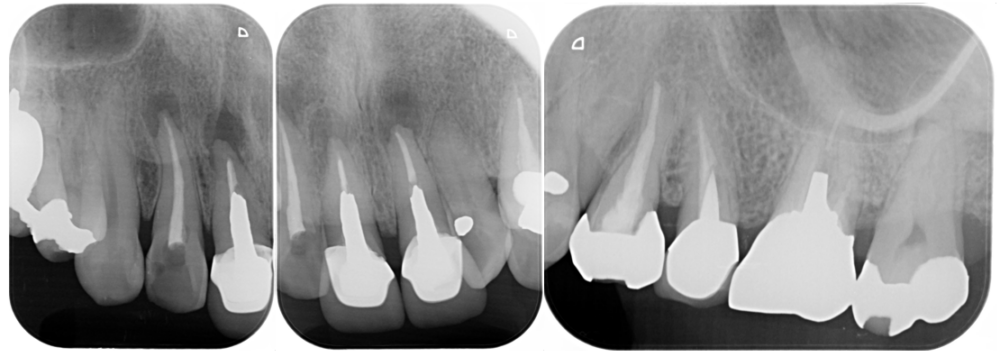

BEFORE |

AFTER |

人為的根穿孔を起こした部分に感染を起こしており、歯周ポケットが9㎜ありました。 ラバーダム防湿とマイクロスコープを使用して丁寧に治療を行いました。 殺菌性があり歯を補強することのできるMTAという根管充填材料を使用して、歯周ポケットは2㎜に改善しました。 |